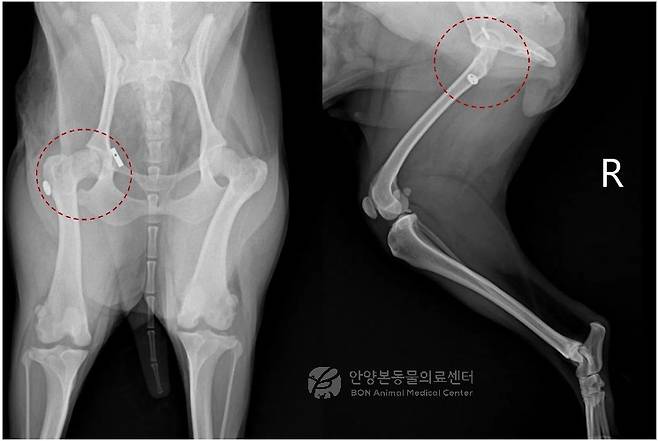

수술은 탈구된 고관절을 노출한 뒤 손상된 인대를 정리하고 인공 인대를 설치해 관절을 제자리로 되돌리는 방식으로 진행됐다. 이후 파열된 관절낭을 봉합하고 고관절의 안정성과 가동 범위를 확인한 뒤 수술을 마무리했다. 수술 후 추적 방사선 검사에서도 고관절은 안정적으로 유지되고 있는 것으로 확인됐다.